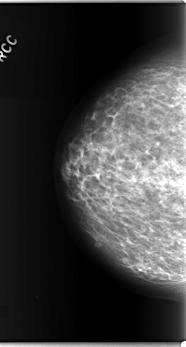

C_0280_1.RIGHT_CC

RIGHT_CC LINES 5888 PIXELS_PER_LINE 3152 BITS_PER_PIXEL 12 RESOLUTION 50 NON_OVERLAY

FILE: C_0280_1.LEFT_CC.OVERLAY

TOTAL_ABNORMALITIES 2

ABNORMALITY 1

LESION_TYPE CALCIFICATION TYPE PLEOMORPHIC DISTRIBUTION CLUSTERED

ASSESSMENT 3

SUBTLETY 5

PATHOLOGY BENIGN

ABNORMALITY 2

LESION_TYPE CALCIFICATION TYPE AMORPHOUS DISTRIBUTION CLUSTERED

ASSESSMENT 4

SUBTLETY 3

LEFT_CC LINES 5976 PIXELS_PER_LINE 2904 BITS_PER_PIXEL 12 RESOLUTION 50 OVERLAY